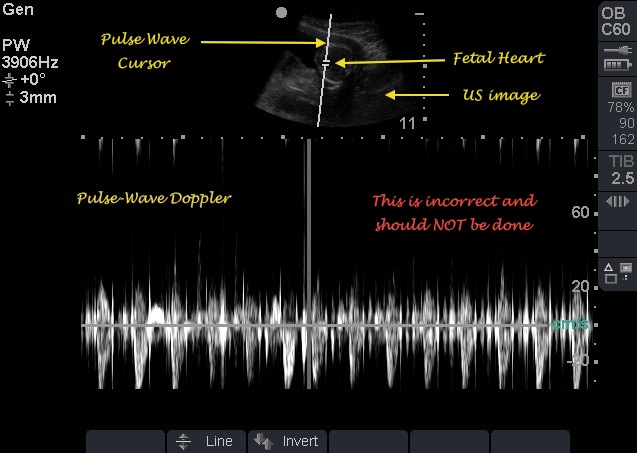

Gambar USG dengan tampilan gelombang detak jantung (M-Mode) | Sumber: Emory School of Medicine

Pada trimester pertama, tanda janin sehat terlihat dari perkembangan organ dan struktur tubuh yang sesuai usia kehamilan, gerakan janin yang mulai terjadi, serta detak jantung yang sudah dapat dideteksi secara ultrasonografi pada minggu ke-12.

1. Detak Jantung Janin Terdengar

Detak jantung janin terdengar adalah momen yang sangat mengharukan dan paling melegakan bagi setiap calon orang tua.

Saat dokter melakukan USG, mendengarkan detak jantung janin untuk pertama kalinya adalah konfirmasi nyata bahwa kehidupan baru telah dimulai.

Umumnya, detak jantung janin baru bisa terdeteksi melalui USG transvaginal pada usia kehamilan sekitar 6–7 minggu

2. Frekuensi Detak Jantung Normal

Setelah terdeteksi, hal berikutnya yang diperhatikan adalah ritmenya. Janin yang sehat dan berkembang baik di awal kehamilan memiliki denyut jantung cepat, biasanya berkisar antara 110 hingga 160 detak per menit (bpm).

Detak jantung yang stabil dan berada dalam batas normal ini menjadi ciri-ciri janin kuat susah keguguran, sehingga menunjukkan sistem vitalnya berfungsi optimal.